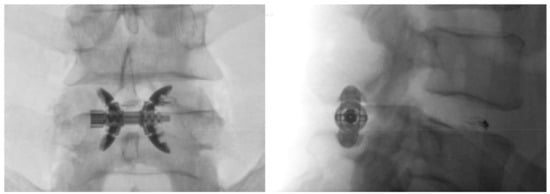

- Bonaldi, G.; Bertolini, G.; Marrocu, A.; Cianfoni, A. Posterior vertebral arch cement augmentation (spinoplasty) to prevent fracture of spinous processes after interspinous spacer implant. AJNR Am. J. Neuroradiol. 2012, 33, 522–528. [Google Scholar] [CrossRef]

- Manfré, L. Posterior Arch Augmentation (Spinoplasty) before and after Single and Double Interspinous Spacer Introduction at the Same Level: Preventing and Treating the Failure? Interv Neuroradiol. 2014, 20, 626–631. [Google Scholar] [CrossRef]